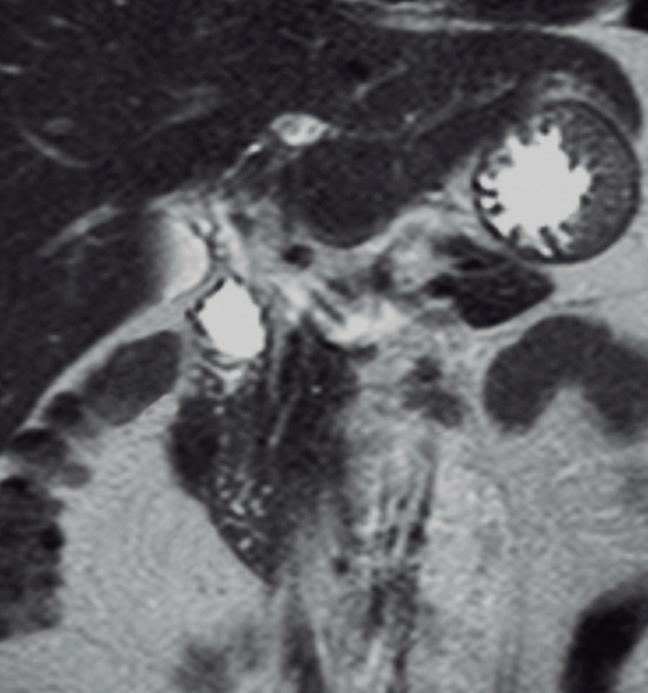

Páncreas Anular

Consiste en una anomalía de la migración del brote pancreático ventral, el cual no rota o lo hace de manera incompleta, resultando en la presencia de tejido glandular pancreático a la derecha del duodeno, rodeando a su 2° porción (Figura 8). Han sido descriptos dos subtipos: el extramural, donde el conducto de Wirsung rodea al duodeno uniéndose al conducto pancreático principal; y el intramural, donde el tejido pancreático se entremezcla con la pared duodenal y sus secreciones drenan directamente a la luz a través de conductos muy pequeños.16

En las imágenes encontramos parénquima pancreático rodeando a la 2° porción duodenal, habitualmente en toda su circunferencia y en ocasiones de manera incompleta. En la colangio-RM es posible visualizar al conducto pancreático a la derecha del duodeno, con un recorrido que se dirige a la ubicación de la papila mayor (Figura 9).17

A) Resonancia magnética secuencia T1 con gadolinio, plano axial. Las flechas señalan el parénquima del páncreas prolongado hacia la derecha “abrazando” a la 2° porción duodenal (cabeza de flecha). B) Resonancia magnética, secuencia T1 con gadolinio, plano axial, corte más caudal al previo. Las flechas nos muestran al páncreas rodeando de manera completa a la 2° porción del duodeno. C) Resonancia magnética, secuencia T2, plano coronal. La flecha señala presencia de parénquima glandular y conducto pancreático a la derecha del duodeno (cabezas de flecha). D) Resonancia magnética, secuencia T2, plano coronal, corte posterior al previo. El páncreas anular y su conducto de drenaje rodean en forma completa al duodeno (cabezas de flecha). E) Colangio-RM. El conducto del páncreas ventral (flechas) hace un giro, rodea al duodeno (cabeza de flecha) y se une al conducto pancreático principal para drenar en la papila mayor. F) Colangio-RM. La imagen magnificada muestra con mayor detalle el recorrido del conducto de Wirsung en el contexto de un páncreas anular.